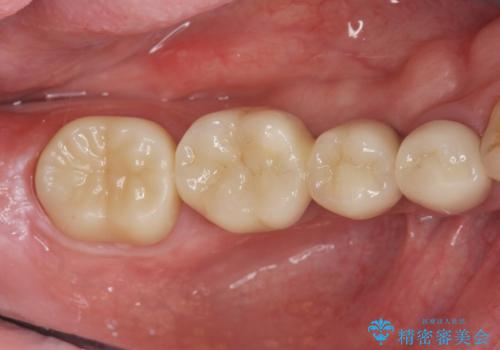

- 105.4万円(仮歯×4・ストローマンインプラント×2・チタンカスタムアバットメント×2・ジルコニアクラウン×4)費用は治療当時の料金となります

インプラント治療は、ブリッジや入れ歯と異なり人口の歯根となるインプラントを顎骨内に埋入することで咬合力に耐える支台を増やせるというメリットがあります。

残った歯の負担を減らすことでより長期的な予後を期待することができます。